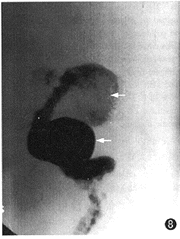

例2 男,38岁。复视,右眼视力下降半年。外院诊断颅咽管瘤,来本中心求治。体检:右外展神经麻痹,右眼视力0.8。CT平扫(图3):鞍旁4.0 cm×3.0 cm×5.0 cm高密度占位,右侧裂内1.0 cm×0.8 cm×1.0 cm高密度占位,边界清,周边呈蛋壳样钙化。MRI示鞍区、鞍上混杂信号占位,边界清,内有流空信号和不同强度短T1、长T2信号,周围脑组织受压水肿(图4,5)。MRA示右颈内动脉蛇形血管通道,累及右大脑中和大脑前动脉(图6)。DSA示右颈内动脉自岩段起呈蛇形迂曲扩张, 累及右M1、A1段及右后交通动脉,血管通道内血流缓慢,静脉窦期仍见对比剂滞留(图7,8)。右颈内动脉球囊闭塞加强试验阴性,但交叉代偿循环充盈试验阳性,先行右颞浅动脉-大脑中动脉搭桥术,术后24 h内,右颈外动脉造影显示吻合口通畅,遂行载瘤动脉近端球囊闭塞术,载瘤动脉闭塞后右颈外动脉造影显示通过吻合口的血流增加(图9)。术后1年随访,症状、体征消失,生活工作正常,CT复查:瘤周脑组织水肿消失,大小无明显变化。

图8 DSA右颈内动脉造影侧位,显示颈内动脉迂曲扩张,累及右A1和后交通动脉,箭头示2个梨形扩张